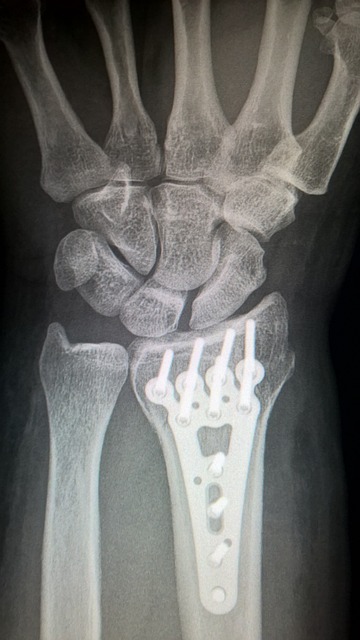

골다공증은 뼈의 밀도가 감소하므로 객관적으로 뼈가 약해지게 됩니다. 이로 인해 일상적인 활동 중에도 간단한 부상이나 낙상에 의해 골절이 발생할 수 있습니다.

갱년기 골다공증으로 인한 후유증 중에서 골절이 발생할 위험성이 높은 부위는 대퇴골(허벅다리 뼈)이나 골반 부위로 여성의 경우, 골다공증으로 뼈의 밀도가 감소하면서 대퇴골이나 골반 부분의 뼈가 쉽게 파괴될 수 있습니다.

특히, 넘어짐이나 낙상과 같은 외부 충격에 노출될 경우 이 부위에서 골절이 발생할 확률이 높아집니다.

갱년기 골다공증이 있는 여성은 골절이 발생했을 때 뼈의 치유가 더 오래 걸릴 수 있습니다. 또한 치유 과정에서 합병증이 발생할 가능성이 높아집니다.

골절로 인한 치유 시간이 길어지면서 통증이 지속될 수 있습니다. 특히, 뼈의 손상이 큰 경우 통증이 심해질 수 있으며 골절 부위의 불편한 움직임을 피하기 위해 주변 근육이 약해지게 됩니다. 이는 움직임의 범위 감소와 관절의 경직을 유발할 수 있습니다.